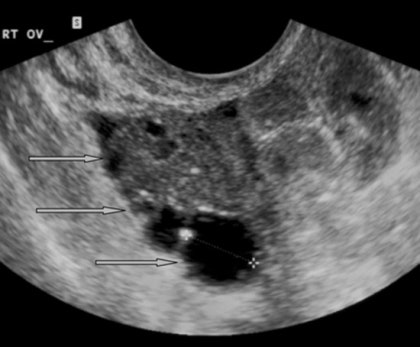

보통 생리가 시작되면 병원에 전화해서 배란초음파 예약을 잡아요. 보통 생리 시작 후 3일째에 오라고 하더군요. 생리 시작 4일째에 방문해서 산전검사(불임검사)를 받고 10일째에 갑니다. 다시 방문하여 모낭의 크기를 확인한 후 후모낭을 터뜨리는 주사를 맞았습니다. 배란초음파법인 후기배란초음파는 질초음파를 이용하여 시행됩니다. 처음에는 당황스러웠지만 의사선생님께서 초음파 모니터를 보면서 말씀해주셔서 실제로 진료를 보면 괜찮다는 느낌이 들고 익숙해졌습니다. 이번달 생리시작 10일째에 배란초음파를 봤습니다. , 충분히 두꺼워진 자궁 내벽에 세 개의 선(삼중선)이 보였고, 난포의 크기도 1.7cm 정도였으므로 배란이 다가오고 있다며 난포를 터뜨리는 주사를 처방했다. 현재는 매달 배란이 잘 되어 약을 처방받은 적은 없지만, 생리 3일째부터 약을 먹기 시작하고, 그 사이에 난포를 키우기 위해 주사를 맞는 경우도 있다고 합니다. 숙제 날짜 배란 초음파 검사를 위해 산부인과에 가는 이유는 정확한 숙제 날짜를 얻기 위해서입니다. 내 경우에는 모낭 주사 당일과 이틀 후, 두 번의 약속을 주셨고, 숙제를 마친 다음 날 돌아왔다. 초음파를 보니 배란이 된 지 얼마 되지 않은 것 같았습니다. 그는 안 한다며 그날 숙제를 한 번 더 하라고 하더군요. 제 자궁에서 정자를 채취해서 자궁경부를 잘 통과하는지 확인하셨어요. 딸을 갖고 싶다고 해서 인지치료가 끝난 뒤 따뜻한 물로 질 내부를 닦아주었다. 이렇게 총 3번 숙제를 했어요. 배란 후 14일째에 월경이 오기 때문에 이번달에 임신이 안되면 다음 월경 3일뒤에 다시 내원하여 배란초음파를 받기로 했습니다. (첫 방문과 달리 생리 종료 후 3일이라는 차이가 있습니다.) 배란초음파 비용 1회 시술에 20,000~30,000원 ​​정도이며, 주사를 맞을 경우 추가 비용이 발생합니다. 오늘은 산부인과에서 배란초음파치료 시기와 비용, 후기에 대해 글을 써봤습니다. 아이를 낳은 뒤에도 산부인과 의사를 선뜻 방문하기가 어려웠다. 배란초음파 치료를 망설이시는 분들에게 이 글이 도움이 되었으면 좋겠습니다.